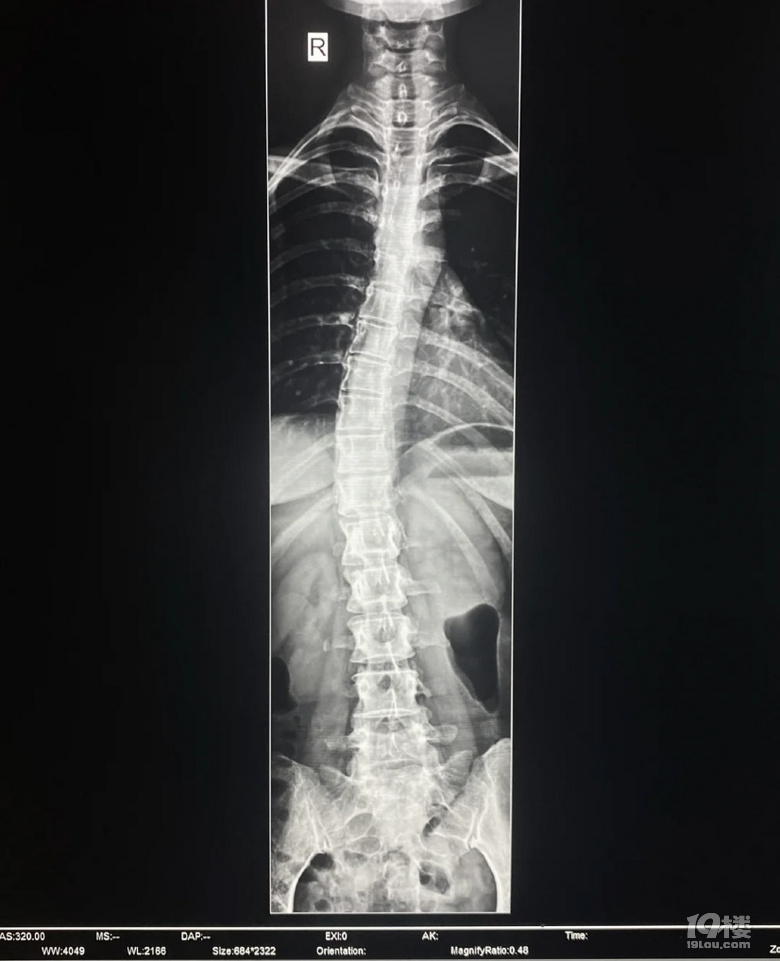

疼得有點(diǎn)熬不住了,上周去骨科掛號,醫(yī)生讓我拍一個全脊柱X正側(cè)位片,果然彎了……大概二十度,不用做手術(shù),當(dāng)時我還在竊喜,省了十多萬的手術(shù)費(fèi),結(jié)果醫(yī)生跟我說了一個更嚴(yán)重的問題,我的頸椎變直了!醫(yī)生說看我頸紋也很明顯,沒少低頭玩手機(jī)吧?我這個年紀(jì)不應(yīng)該是這樣的頸椎,六七十歲的人才會這樣。